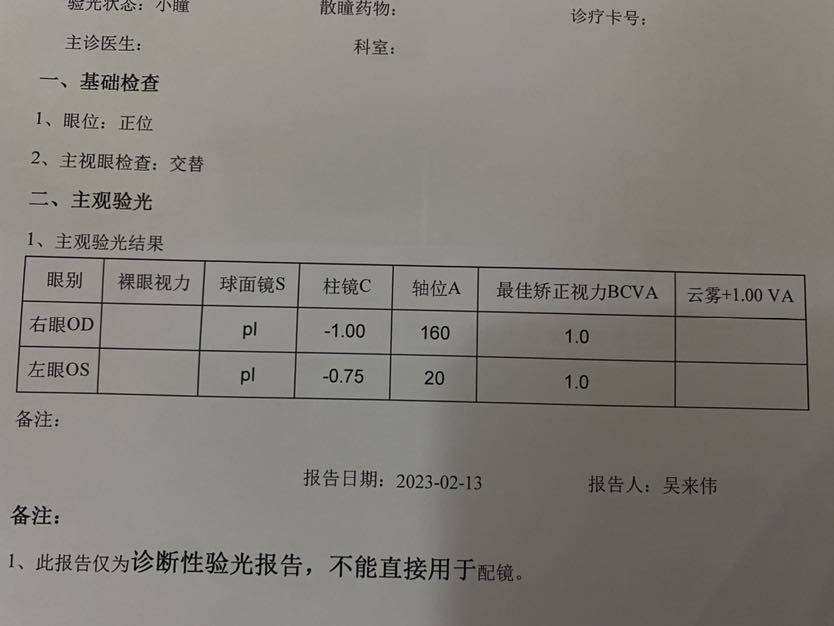

【小瞳验光】 【眼部彩色照】

【小瞳验光】